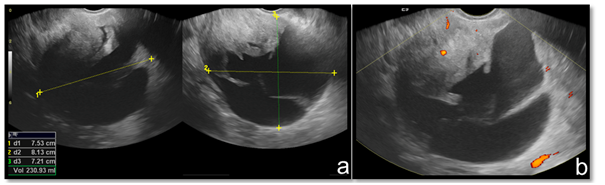

A 71-year-old woman developed clinically gluteal cellulitis. During the diagnostic investigation by transvaginal pelvic ultrasonography, a multiloculated pelvic solid and cystic lesion was detected, with septations and scarce blood flow to color Doppler (Figure 1). This exam couldn’t define the original site of this lesion. Pelvic magnetic resonance imaging (MRI) revealed a large pelvic solid and cystic formation with well-defined limits and an important cranial and anterior dislocation of the uterus and bladder (Figure 2). Retraction of the right ischiorectal fossa fat through the lesion and towards the pelvic cavity was detected (Figure 3) and represented a decisive information in the diagnostic investigation. Patient underwent surgical resection with complete excision of the tumor and evolved well in the postoperative (Figure 4). The histopathological examination revealed a neoplasm characterized by a densely collagenized stroma with alternating zones of cellularity, consisting of small spindled or ovoid cells with moderate amounts of eosinophilic cytoplasm and nuclei with fine chromatin and inconspicuous nucleoli, clustered around thin-walled capillaries (Figure 5). The immunohistochemical study revealed diffuse expression of desmin as well as estrogen and progesterone receptors, corroborating the diagnosis of angiomyofibroblastoma. There is no sign of tumor recurrence in periodic imaging exam less than one year after surgery.

Figure 1 Transvaginal pelvic ultrasound. Solid and cystic expansive formation (A). Scarce blood flow to color Doppler (B).